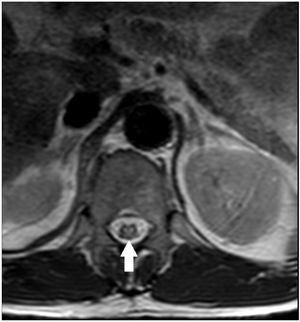

We present the case of a 63-year-old man with liver cirrhosis of mixed aetiology (alcoholic and hepatitis C virus infection) and a diagnosis of a 14-mm hepatocarcinoma in segment III and 40 mm in segment VI. Transarterial chemoembolisation (TACE) of hepatocellular carcinoma was performed by super-selective catheterisation of the feeding arteries of the tumour nodules and they were embolised with doxorubicin (DC-Beads 100−300 μ and 300−500 μ) (Fig. 1). Following the procedure, he developed symptoms consistent with urinary retention, paraesthesia and paresis in both lower limbs with the inability to walk. In the emergency thoracolumbar MRI performed due to suspected spinal cord ischaemia after TACE, an increased signal was observed in the distal portion of the cord and the conus medullaris with moderate restriction in the diffusion sequence (Figs. 2–4), possibly related to an acute ischaemic injury at the level of T11, which was confirmed. Following rehabilitation, the patient was discharged with preserved ambulation.

TACE is based on the almost exclusively arterial vascularisation of the hepatocarcinoma.1 In our patient, the clinical symptoms were accounted for by the existence of an artery feeding the tumour collaterally to one of the spinal arteries that supply the spinal cord, with the chemotherapeutic material entering the spinal cord and inducing unusual transient acute spinal cord ischaemia.